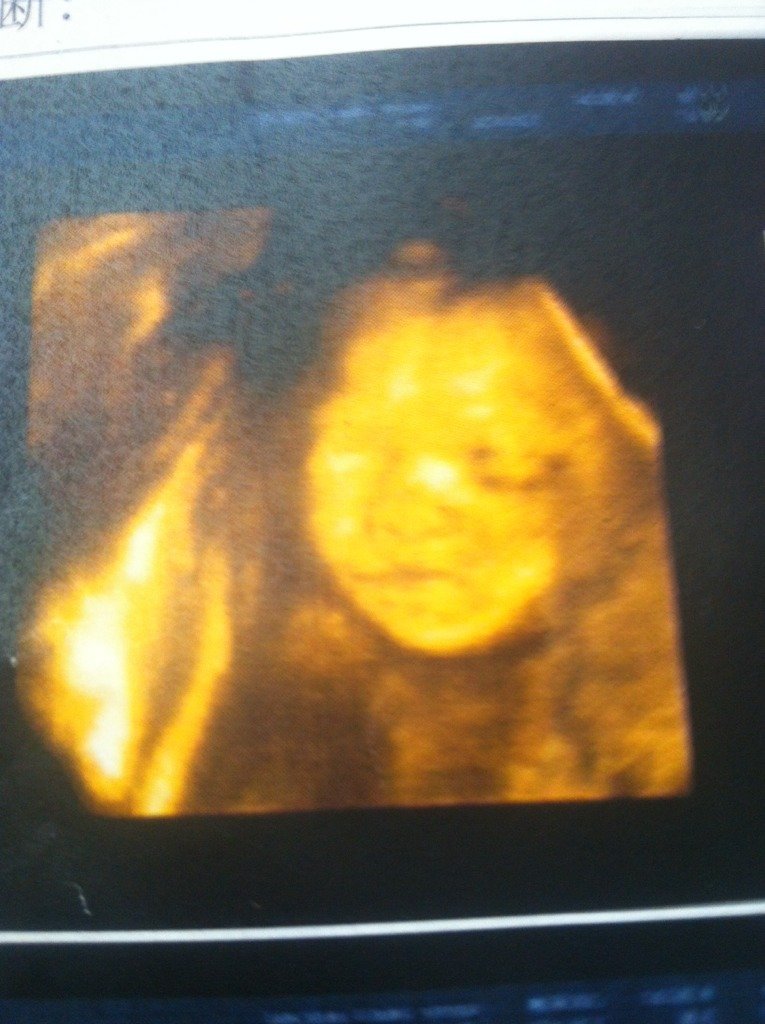

谁能帮我看看是男孩女孩,男女我都喜欢 谁能帮我看看是男孩女孩,男女我都喜欢 点击展开 亲亲乐乐 2014-08-02 15:15 为您推荐: 其他回答 看不出来的,医生扫到的生殖器切面是不会显示在这张报告单上的。 咱微笑0606 2014-08-02 18:33 这个事宝宝的脸部,没法判断男孩女孩,要看宝宝的第一性征才可以。 咱微笑0606 2014-08-02 16:18 相关问题 谁能帮我看看,是男孩女孩啊,特别好奇哦 57天孕囊大小3 1*3 2*2 0胎心148谁能帮我看看男孩女孩 怀孕两个月零十天了,想知道是男女 下面是我的彩超检查结果 懂得帮我看看男孩女孩 超声描述:子宫后位